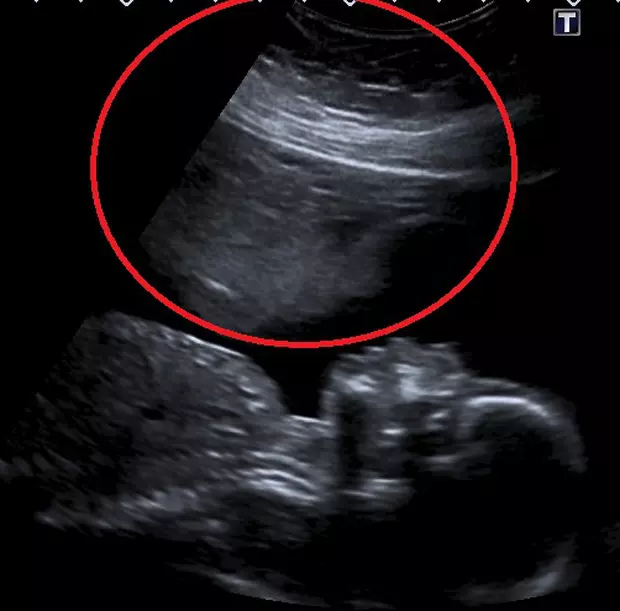

Stacey Astley (38 de ani), din Tauton, Someset, Marea Britanie, susține că a văzut chipul unui înger în ecografia de 20 de săptămâni a bebelușului pe care-l aștepta. Femeia mai are patru copii și a pierdut trei sarcini în încercarea de a-l face pe cel cu numărul cinci. Stacey spune că îngerul păzitor din ecografie a ajutat-o să aducă pe lume copilul pe care și-l dorea și pe care îl credea imposibil de făcut după pierderile de sarcină.

„La scanarea mea de 16 săptămâni, hematomul a scăzut în cele din urmă, iar la scanarea mea de 18 săptămâni a scăzut la jumătate din dimensiunea inițială. Sângerarea s-a oprit la 19 săptămâni, iar această fotografie cu îngerul păzitor a fost făcută la 20 de săptămâni.

După toate greutățile prin care am trecut înainte de concepere şi prin cele pe care le-am experimentat împreună cu fătul, în timpul sarcinii, cred că acolo a fost ceva sau cineva care s-a uitat la noi de această dată şi ne-a dat o mână de ajutor. Nu ştiu ce sau cine a fost. Sau poate a fost doar noroc. Dar voi rămâne recunoscătoare pe viaţă pentru că a ajutat ca fiul nostru să rămână cu noi', a mai spus Stacey.